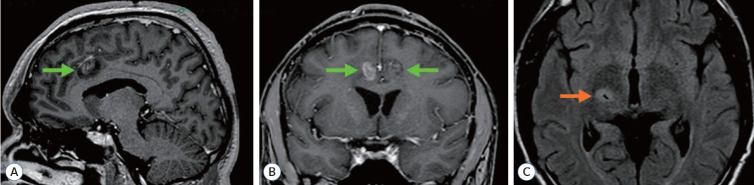

Stereotactic bilateral anterior cingulotomy, including lesions in the anterior and midcingulate cortex, is one of the methods used for treating thalamic pain syndrome. In cases of non-ischemic thalamic lesions, simultaneous stereotactic biopsy of the lesion can be performed in combination with cingulotomy. In this paper we present a case of a 45-year-old male with a lesion in the right thalamus, causing a severe contralateral hemi-pain syndrome. Bilateral radiofrequency anterior cingulotomy and stereotactic biopsy were performed during a single surgery. Pain completely subsided within a few days following the anterior cingulotomy. Histological examination identified a diffuse astrocytoma (World Health Organization grade II, ICD-O 9400/3), and the patient was subsequently referred for LINAC-based radiosurgery. The pain syndrome was controlled for 4 years, after which the pain syndrome returned with an increase in tumor size. Simultaneous anterior cingulotomy and stereotactic biopsy of the thalamic lesion represent a safe intervention for thalamic pain syndrome, enabling the alleviation of pain, verification of the lesion's etiology, and the application of appropriate treatment.

Abstract Image